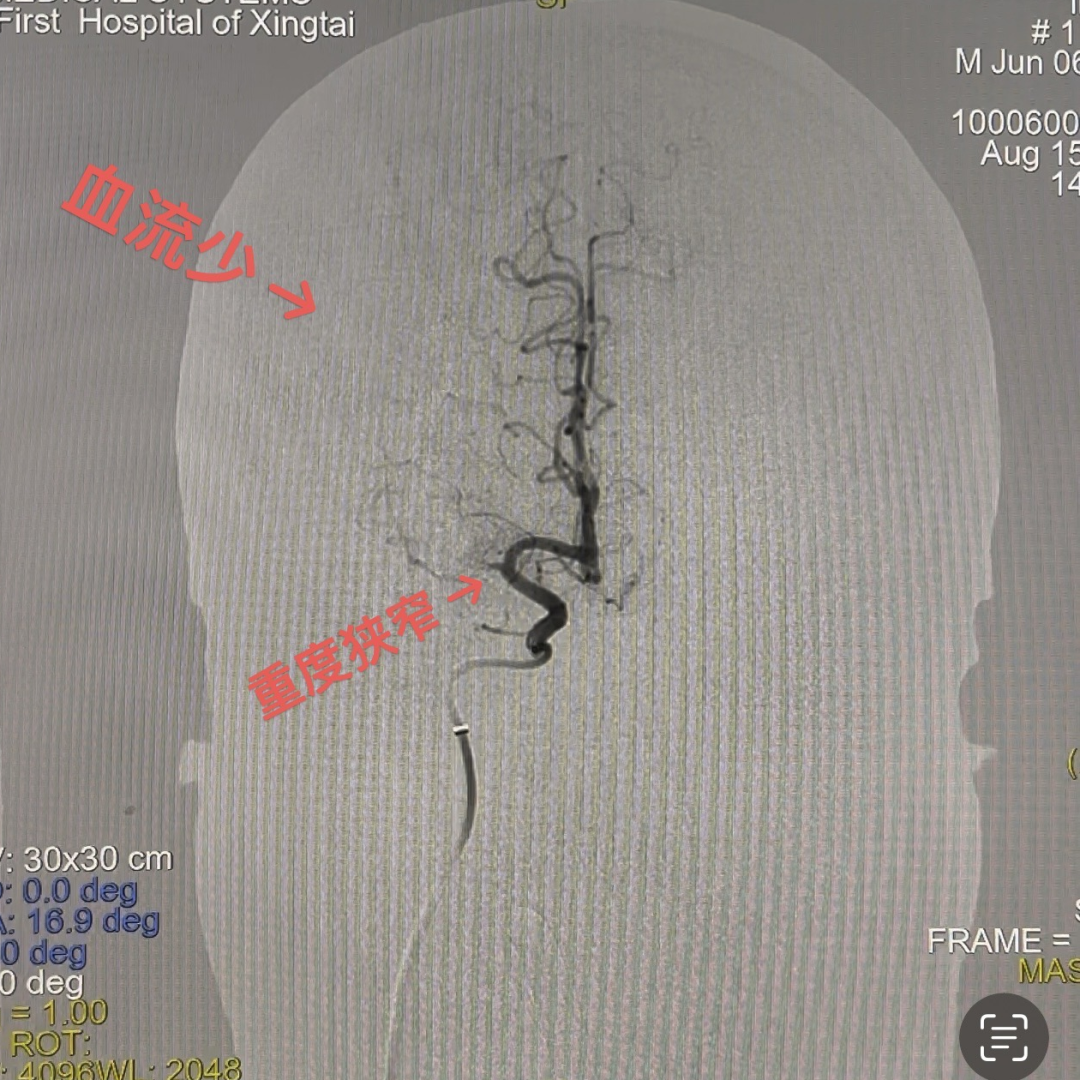

DSA提示患者右侧大脑中动脉狭窄率约95%;PWI提示右额颞顶叶低灌注。

动脉长鞘怎么置入一技之“长”丨经桡及经股困难入路应用赛诺神畅APEX TRA GC™导引导管建立通路病例合集_https://www.jmylbn.com_新闻资讯_第26张

动脉长鞘怎么置入一技之“长”丨经桡及经股困难入路应用赛诺神畅APEX TRA GC™导引导管建立通路病例合集_https://www.jmylbn.com_新闻资讯_第31张

动脉长鞘怎么置入一技之“长”丨经桡及经股困难入路应用赛诺神畅APEX TRA GC™导引导管建立通路病例合集_https://www.jmylbn.com_新闻资讯_第32张

头PWI

DSA